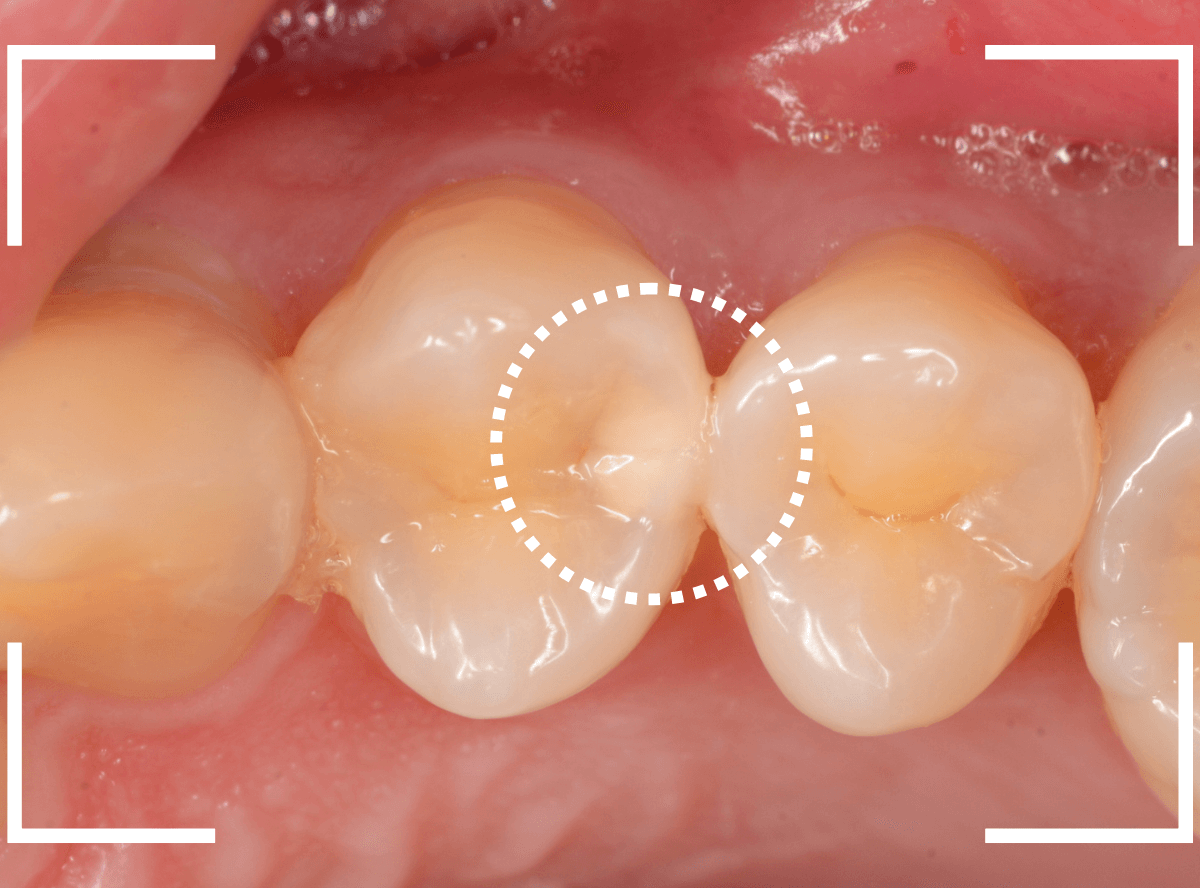

Case.10 レントゲン写真でしか虫歯がわからなかったケース

検診希望で来院された患者さんの例です。

レントゲン写真で、後ろの歯との間に虫歯が見つかりました。

大きな虫歯になっていると考えられます。

上から見ただけでは私でもどこが虫歯かわかりません。

今回はレントゲン写真で明らかに判別できましたが、虫歯の診断はドクター間でも意見が別れる時があるほど、奥深く難しいです。

自己判断はくれぐれも禁物です。